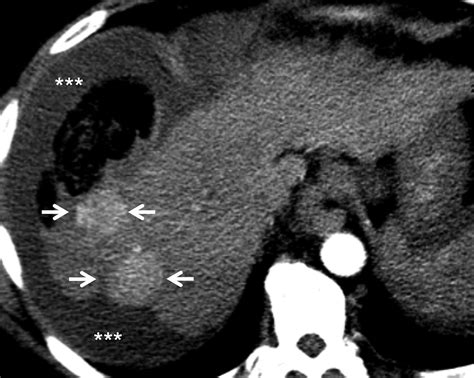

Modern diagnostic imaging relies heavily on this anatomical distinction. Computed Tomography (CT) scans are the gold standard for identifying exactly where a pathology is localized. When a radiologist reviews an abdominal scan, they assess the presence of fluid—such as blood, bile, or pus—to determine if it is confined within the retroperitoneum or if it has extravasated into the broader peritoneal cavity. Knowing whether a mass or lesion involves intraperitoneal vs retroperitoneal tissues directly dictates the biopsy technique or surgical resection plan, as approaching retroperitoneal structures often involves bypassing the major vessels or kidneys located in the posterior space.